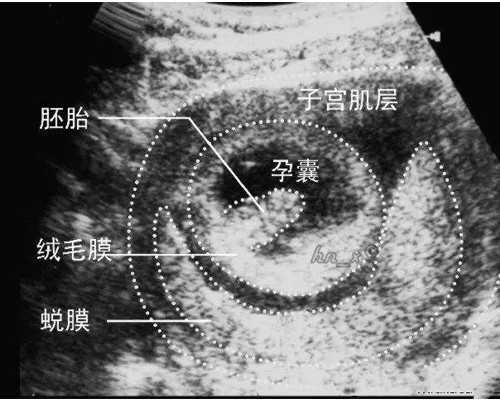

试管ivf|二移时间确定(自然周期) 代孕试管费用

这次走的自然周期,因为我还想尝试自怀姨妈第11天开始第一次抽血监测排卵一周之内抽了4次[哭惹R][哭惹R][哭惹R]胳膊都淤青了,幸好终于排卵了…中间还做了一次b超怕自己紧张,激素、内膜、卵泡检查结果我都没问…一切随天意,跟着医生指示走明天又可以去接我的宝宝回家啦![暗中观察R] #试管之路[话题]......